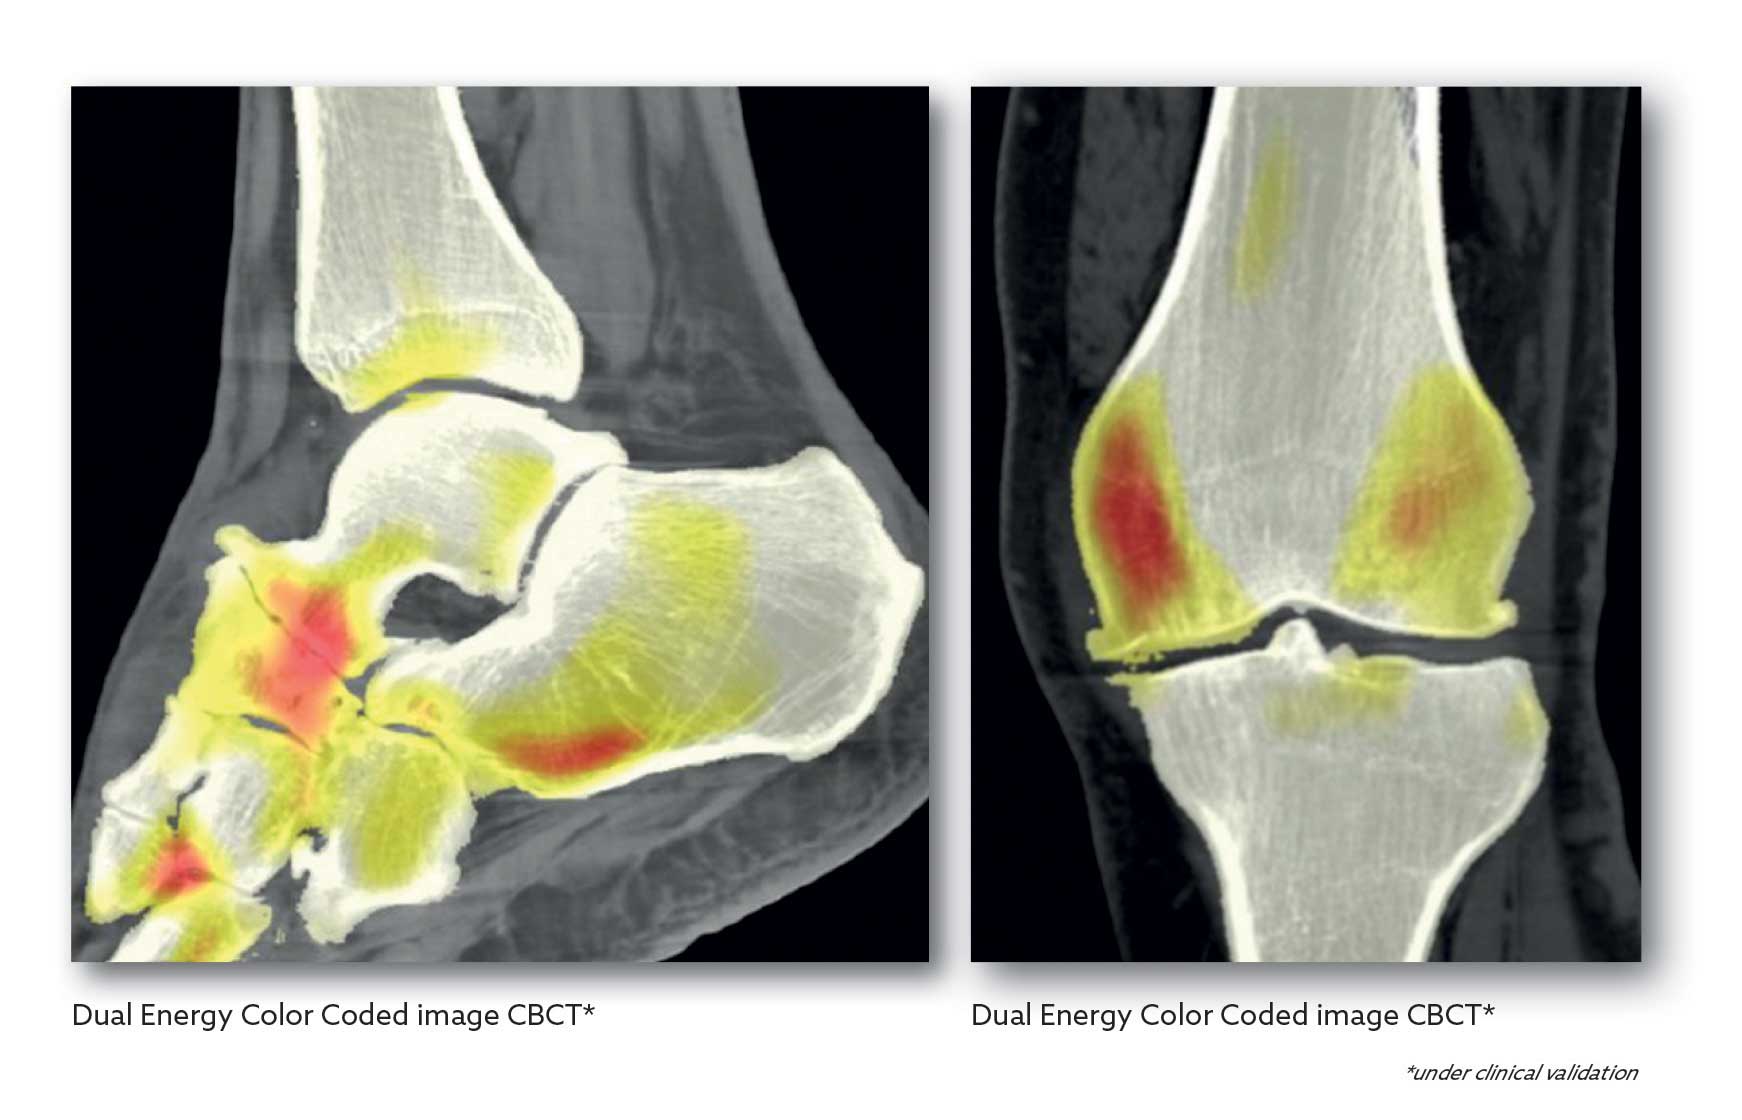

NEWTOM’s Dual Energy software enables users to perform semi-automatic tissue segmentation and the application of colour-coded images, streamlining the differentiation of materials within the scanned area. This allows rapid and straightforward detection of potential pathologies.

Quantitative tests have demonstrated that, compared to single-energy CBCT exams, Dual Energy protocols improve HU accuracy, contrast resolution and image homogeneity.

One of the causes of image quality decay is the appearance of artifacts caused by patient movement. NEWTOM has developed an algorithm that corrects any movement-induced distortions. It does this on each axis, offsetting any shifts, rotations or variations in distance from the panel. So, the new features enable weighted blending of high- and low-energy imaging. The resulting images combine the low noise typical of high-energy acquisition with the high-contrast resolution of the low-energy image set. NEWTOM’s Dual Energy technology provides unique clinical information that lets you highlight, characterise, quantify and distinguish tissues, which have different sensitivities to different energy levels, within the areas being scanned. This delivers supplementary information about the chemical composition of the materials in the area being examined, thereby helping physicians make more accurate diagnoses.